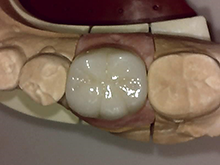

オールセラミックス

金属を使わずに全てセラミックを使用し、光の透過性を上げる事により自然な白い歯に回復させる方法です。

現在では土台から白い材質(ファイバーポストなど)の物を使用することにより、さらに透明感が増し天然歯に近似しています。

オールセラミックは近年進化を遂げており、強度や接着性がかなり改善され、審美的にとても優れたものと成って来ております。

オールセラミックにも色んな種類がありますが、当院ではe-max(二ケイ酸リチウムガラスセラミック、)ジルコニアセラミックスを採用しています。